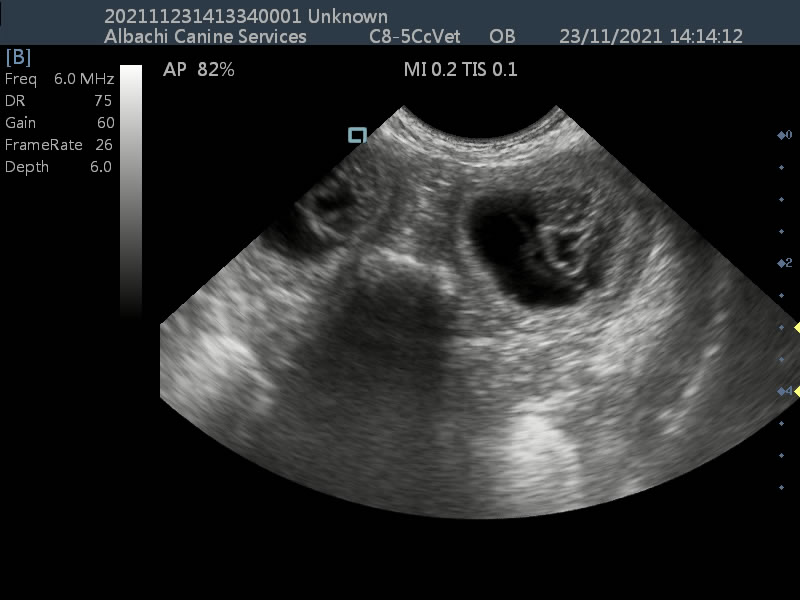

First scan for pumpkin the chihuahua.